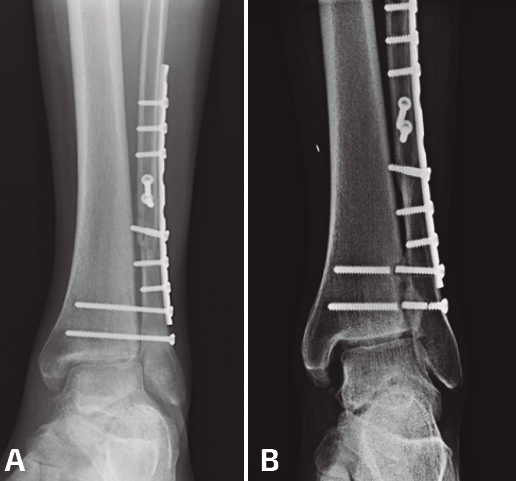

Figura 1. Fractura del maléolo peroneo sintetizada con placa anatómica y sistema TightRope® a los 2 años de seguimiento con correcta reducción de la mortaja y la sindesmosis.